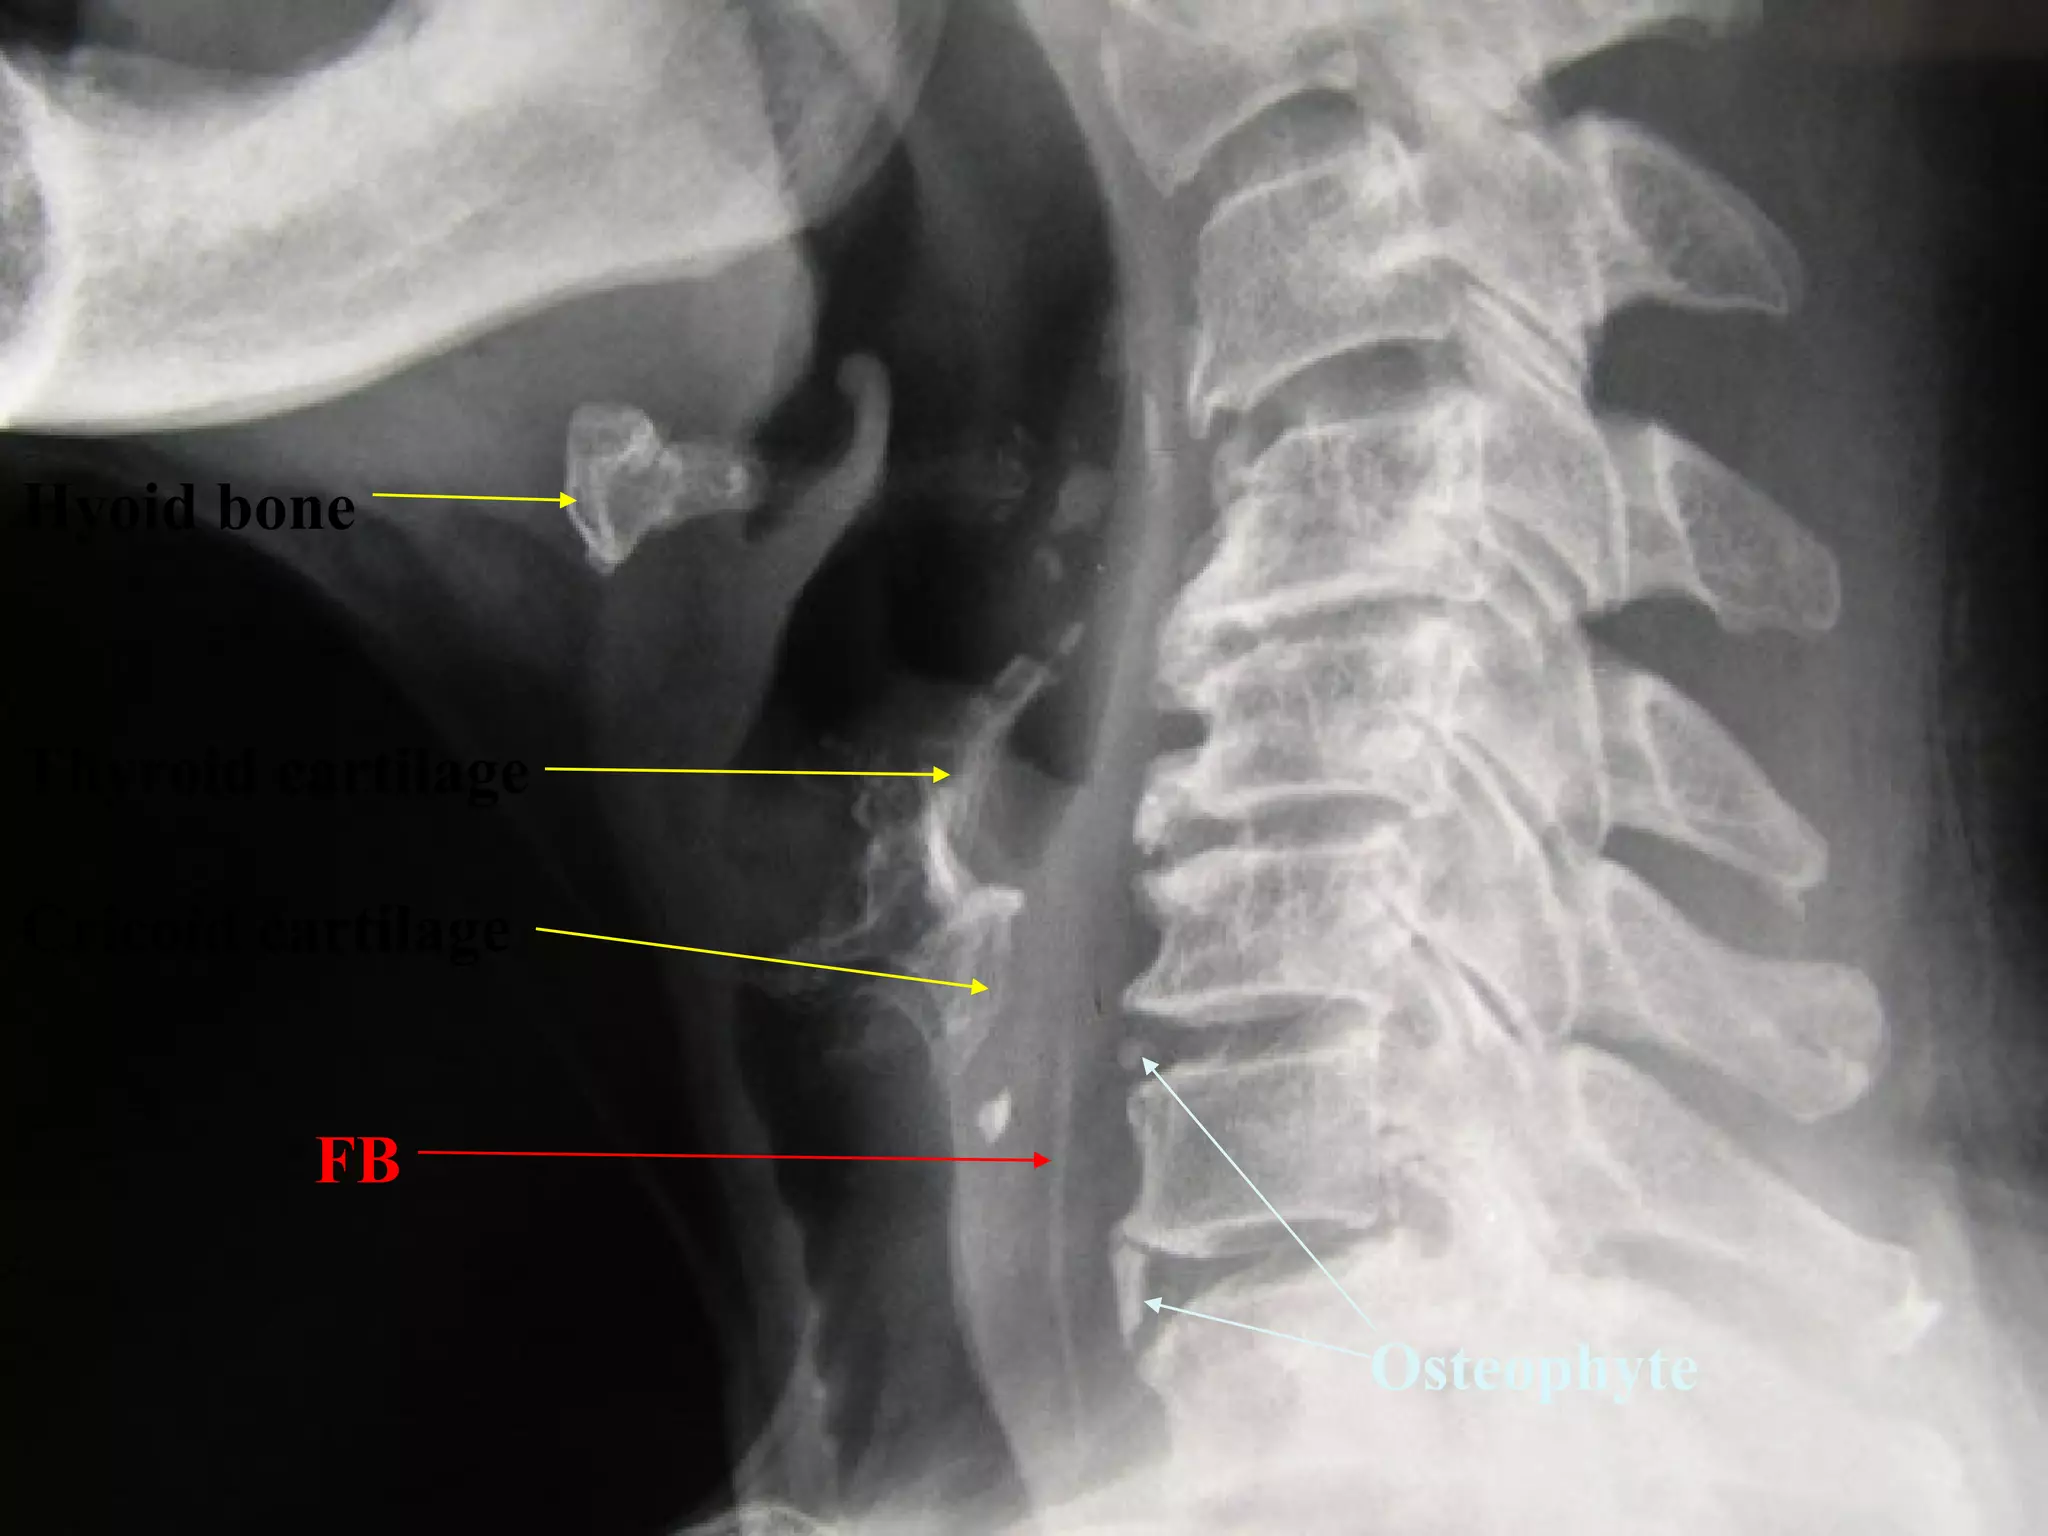

FB Throat - Investigations

Lateral neck XR

CXR

Barium swallow

CT scan – without contrast

Rigid oesophagoscopy

FB

Hyoid bone

Thyroid cartilage

Cricoid cartilage

Osteophyte